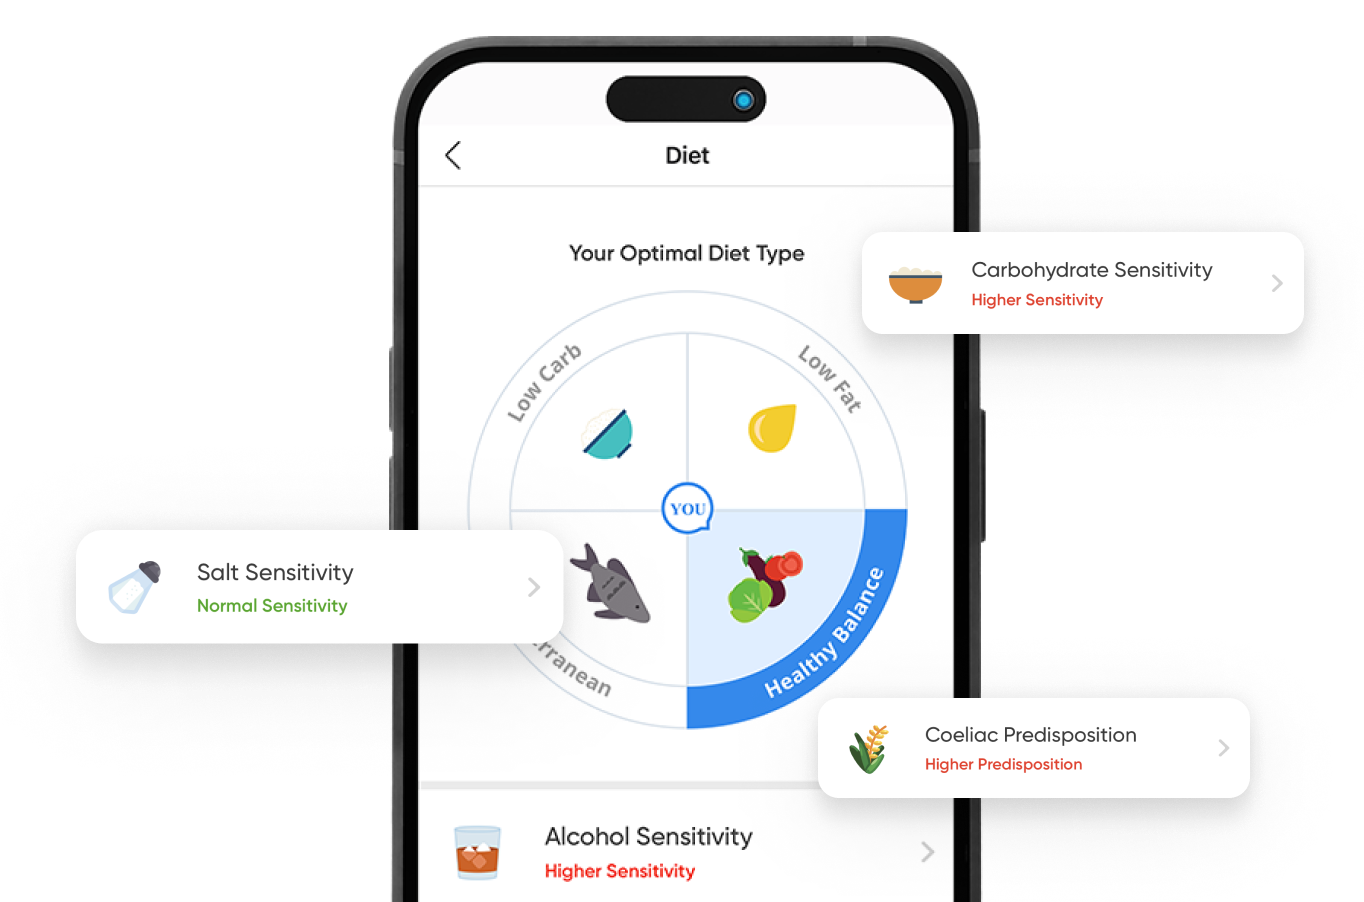

Identify inherited risk markers long before symptoms appear and take decisive, evidence‑based steps early to build a resilient foundation for lifelong health.

The CircleDNA test offers a comprehensive analysis of your genetic makeup, providing valuable insights into various aspects of your health and well-being. This test covers a wide range of areas, including genetic predispositions to certain health conditions, traits related to nutrition and fitness, and carrier status for inherited diseases. Additionally, it provides personalized skincare recommendations, dietary guidance, and ancestry information.

For example, the test can reveal sensitivities to different food groups, enabling you to make more informed dietary choices. It also estimates your lifetime genetic risk of developing certain disorders, offering a thorough overview of potential health risks.